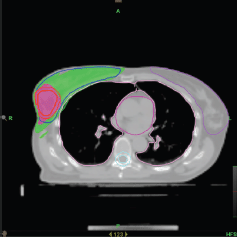

IMRT/IMAT techniques make it possible to deliver different levels of dose to different parts of the tumour (for instance, a hypoxic area of the tumour, identified by means of functional imaging, may receive a boost dose). Approaches using a simultaneous integrated boost (SIB) and the delivery of dose-escalated conventionally fractionated or hypo-fractionated RT using IMRT techniques are now being investigated as an alternative to conventional RT for different anatomical sites: breast [49, 50], head and neck [51, 52] prostate [53, 54]. Examples, using tomotherapy, of SIBs delivered to the breast tumour bed and to the dominant intra-prostatic lesions (DILs) are shown in Figures 1 and 2.

Figure 1. Axial view of a treatment plan for whole breast irradiation with SIB delivered with TomoTherapy. The colour green corresponds to 95% of the prescribed dose to the breast, and the colour red to 95% of the boost dose.